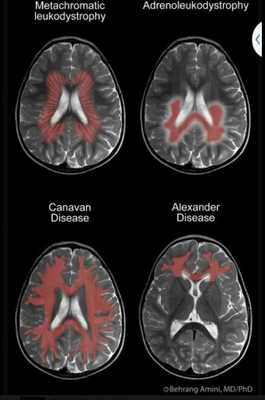

Компьютерная диагностика энцефалопатии

Для диагностики мозговых болезней у детей рациональнее применять МРТ (при возможности сохранения неподвижного положения 15-30 минут). Диагноз энцефалопатии устанавливается после КТ и МР-сканирования. Определяют выбор индивидуальные особенности человека, поставленные диагностические задачи. Информативность способов при правильном подходе можно считать аналогичной.

Ишемические и атрофические изменения четко не прослеживаются при компьютерном сканировании. Состояние обуславливает сопутствующие патологические процессы, на основе которых устанавливается диагноз:

- Диффузные изменения мозговой структуры;

- Расширение желудочков;

- Изменения субарахноидального пространаства;

- Утолщение субкортикального слоя;

- Патологические участки в сером и белом веществе;

- Наличие постишемических кист;

- Лакунарные инсульты (мозговые кровоизлияния).

Дисциркуляторная энцефалопатия сопровождается множественными сосудистыми расстройствами. На основе комплекса нарушений ученые пытаются создать КТ-маркеры, выявление которых позволяет с высокой степенью достоверности установить диагноз.

Важные КТ признаки энцефалопатии:

- Отложение холестерина внутри мозговых артерий. Чем обширнее поражение, тем вероятнее энцефалопатические расстройства;

- Наружная и внутренняя гидроцефалия - скопление жидкости, приводящее к увеличению внутричерепного давления;

- Изменения субкортикального слоя.

- Атрофические, ишемические очаги разной локализации.

Для подтверждения диагноза энцефалопатии сравниваются компьютерные и магнитно-резонансные признаки нозологии. На томограммах за участки атрофии можно принять кисты, неполные инфаркты.

Важный КТ критерий энцефалопатии - феномен лейкоареолизиса. Патология выявлена в 1987 году. После внедрения компьютерного сканирования в медицину обнаружение очагов ишемии размерами до 5 мм в белом веществе при отсутствии гиподенсных участков мозолистого тела, базальных ганглиев, зрительной лучистости вызывало дискуссии у врачей. После использования вентрикулометрии выявлялась гидроцефалия. Комплекс расстройств описывал цереброваскулярные и дисциркуляторные нарушения мозга. Повторное использование способа указывает на прогрессирование гидроцефалии.